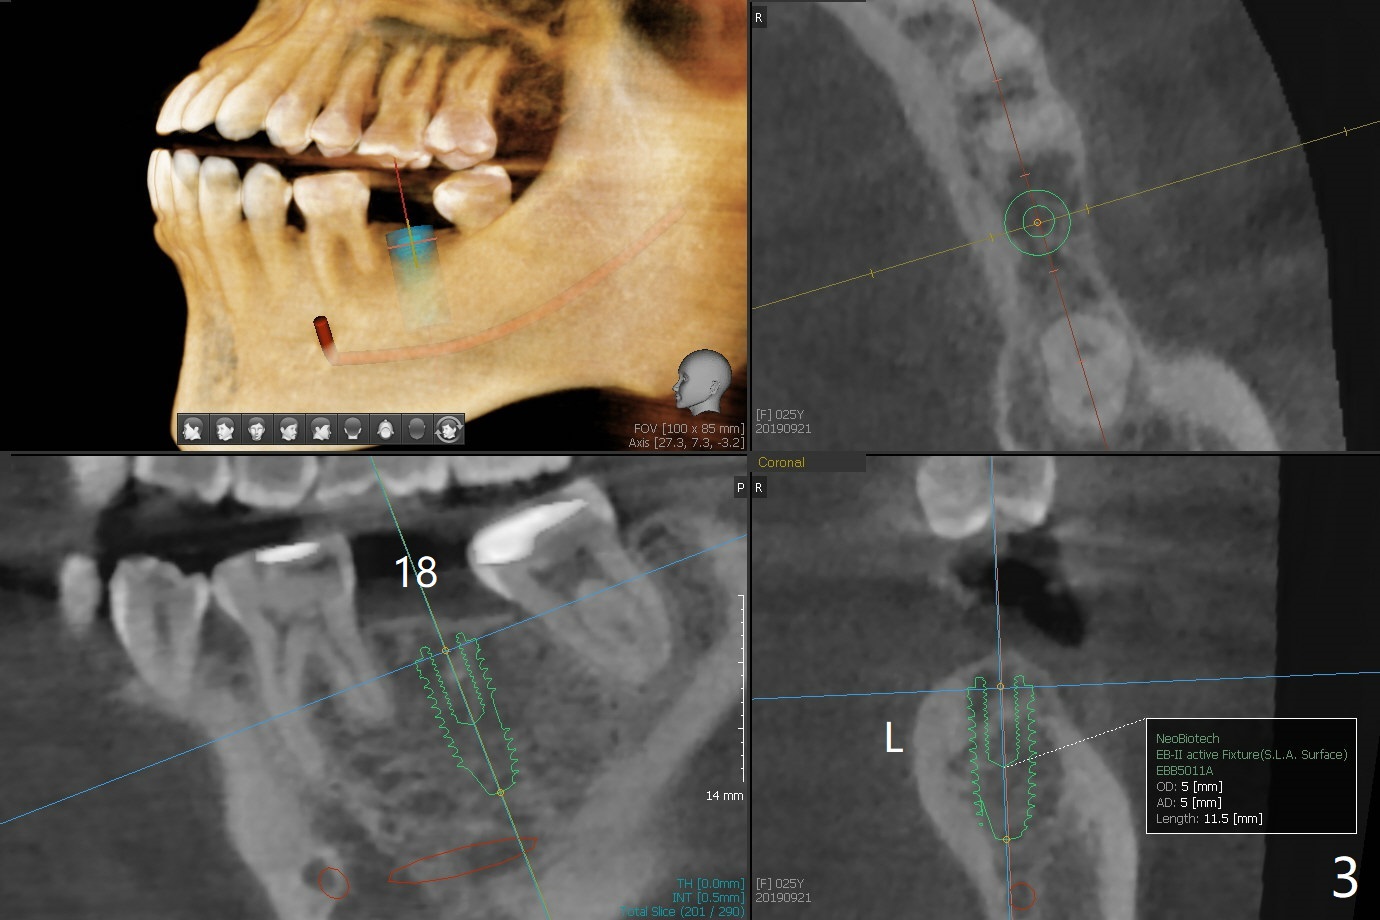

A 25-year-old woman had #2 and 18 extracted ~ 1 year ago (Fig.1). Because of the short and loose bone at #2, a short implant will be placed with sinus lift (PRF, Fig.2). If needed, probe mesiobuccal aspect of the osteotomy when it is close to the sinus floor to detect early sinus floor perforation before water lifting. It would be safer to use water lifting after the 1st sinus safe drill is used. Then water lifting and the 2nd sinus safe drill, et al. To reduce micromovement, a healing screw will be most likely placed instead of a healing abutment. In contrast, a healing abutment is possible at #18 (Fig.3).

Return to Upper Lower Molar Immediate Implant, Trajectory II Xin Wei, DDS, PhD, MS 1st edition 09/21/2019, last revision 02/02/2020